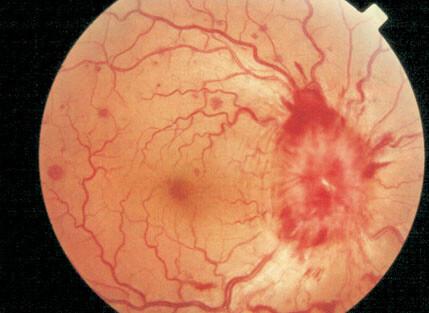

Edema de papila progresivo, comenzando por una papila hiperémica, luego pasa a ser edematosa y por último hipertrófica.